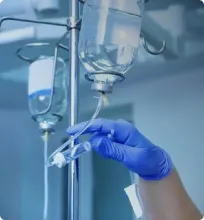

Медикаментозная терапия лудомании

Кроме психотерапии, в лечении лудомании применяется и медикаментозная терапия. Применяются следующие группы фармацевтических препаратов:

- Антидепрессанты, предпочтение отдаётся селективным ингибиторам обратного захвата серотонина. Препараты данной фармацевтической группы уменьшают тревожность, снижают влечение к игре, улучшают психоэмоциональное состояние и качество жизни пациента.

- Антагонисты опиоидных рецепторов. Воздействуют именно на тягу к игре, уменьшают вовлечённость пациента в зависимость.

- Нормотомики. В ходе нескольких исследований была подтверждена эффективность лекарственных средств как при монотерапии, так и при комбинированном воздействии.

- Антагонисты NMDA-рецепторов. Также снижают влечение пациента к зависимости, способствуют сохранению социальности индивида.

Механизм действия лекарственных средств на патогенетические основы лудомании остаётся неизученными, решение о назначении препарата может принимать только лечащий врач.